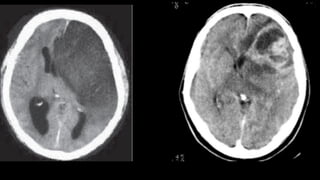

2) Lesões focais com efeito de massa

❑ Início: processo localizado / assimetrias ao exame

❑ Com aumento de PIC 🡪 Herniação

❑ Quadro com piora progressiva

❑ Obs: respostas motoras assimétricas e movimentos oculares anormais persistem

até estágios terminais

❑ Grau de alteração de consciência é relacionado a grosso modo com volume de

tecido cerebral afetado